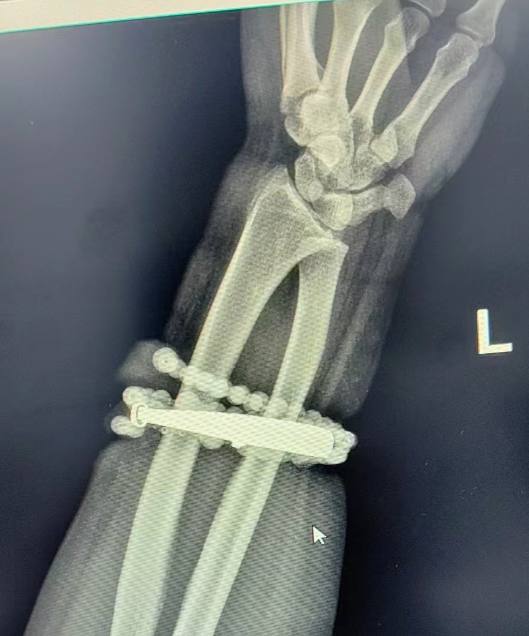

經(jīng)過一個多小時的手術(shù),醫(yī)生們將手鐲和串珠從厚厚的增生組織中完整剝離出來。目前,龔女士恢復良好,已順利出院。